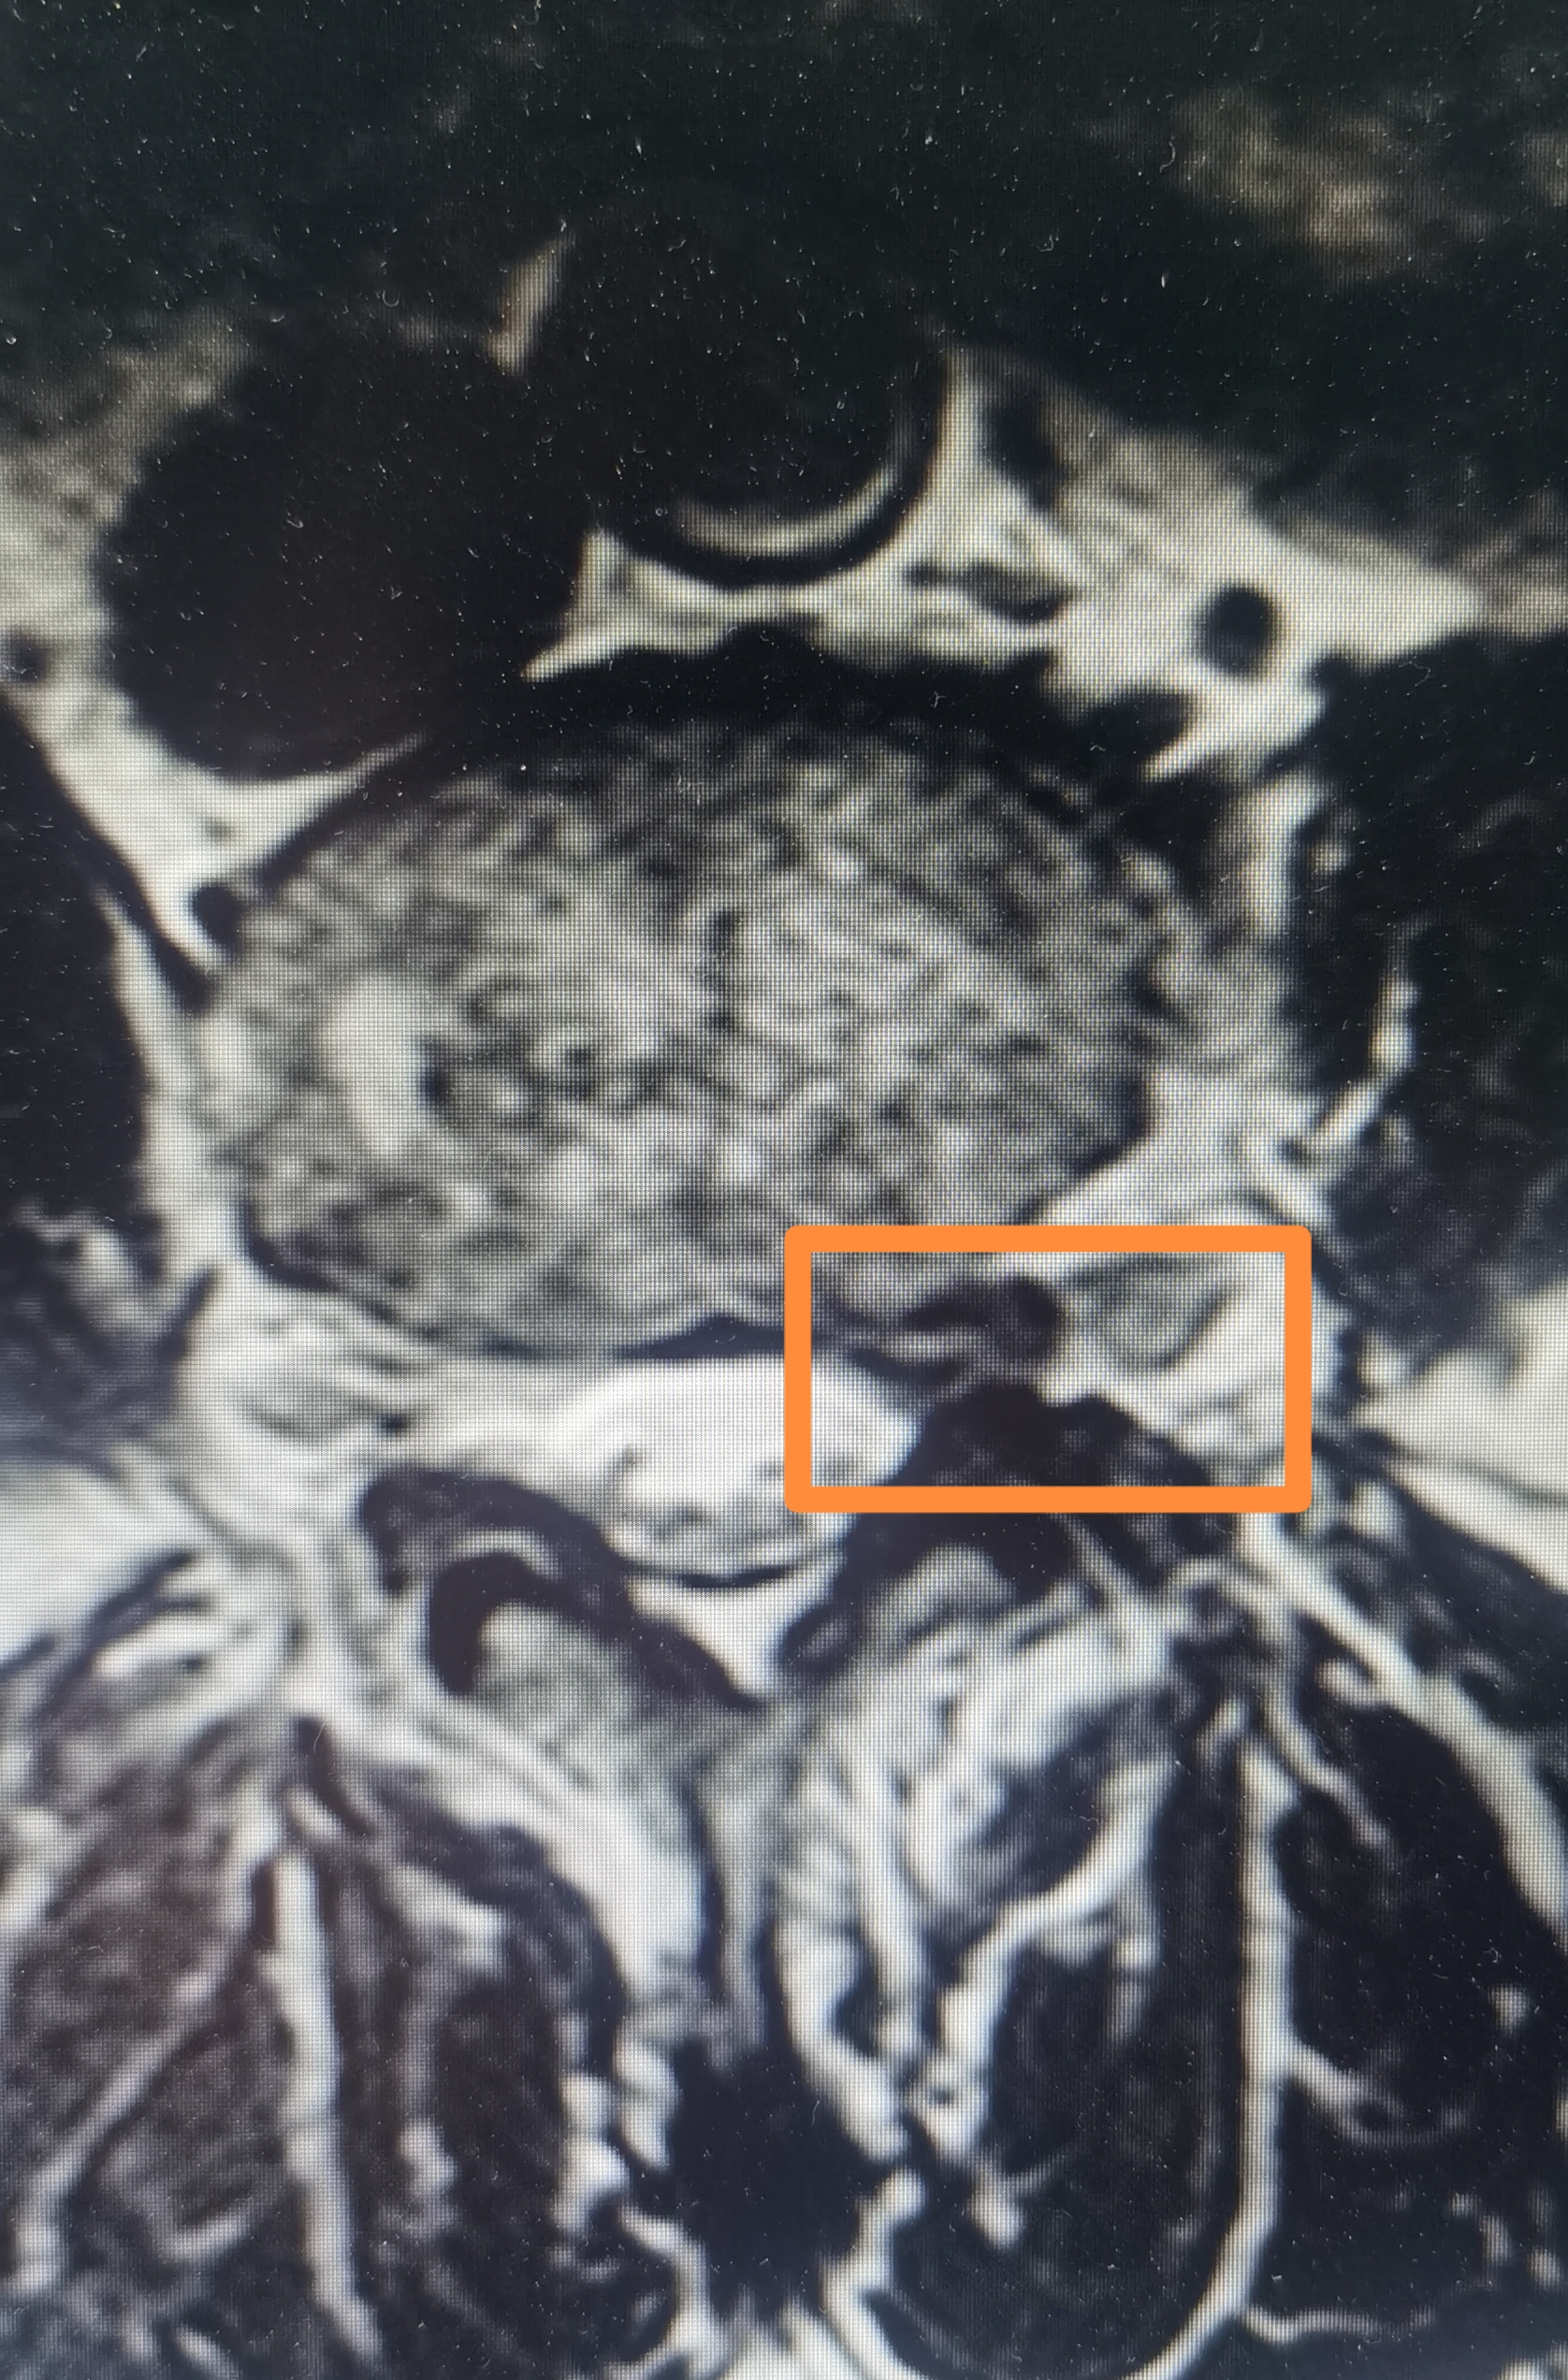

插入《磁共振和 CT 椎间盘脱出》图片